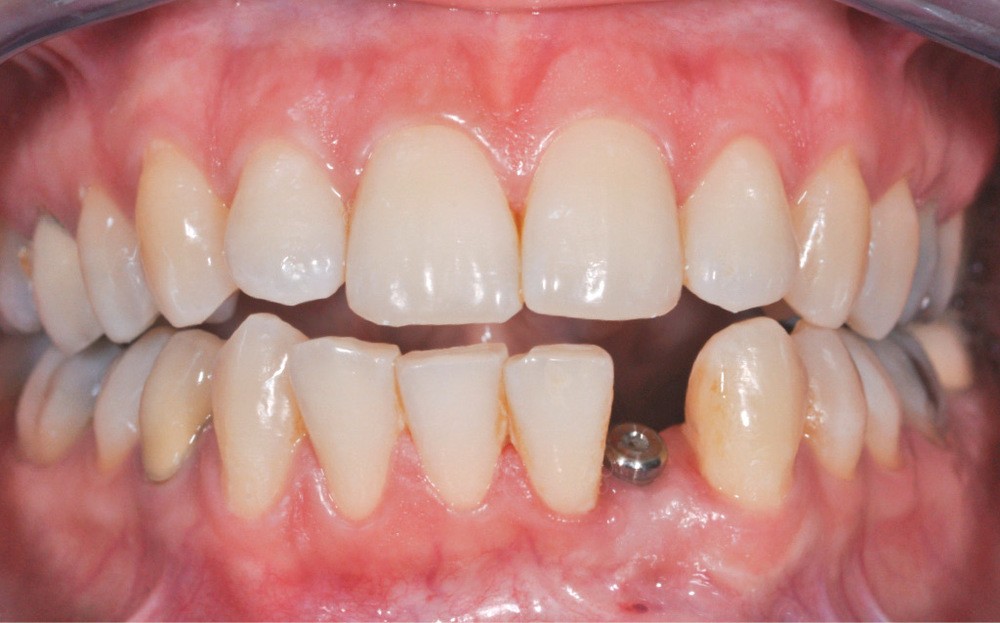

La seconde complication, plus grave, est le risque d’oublier des excès de ciment au niveau sous gingival. Ces derniers sont la cause principale avérée des péri-implantites et des pertes osseuses (fig. 2). Il est donc nécessaire de prendre toutes les précautions pour limiter au maximum ce risque.

Il est indispensable de faire un contrôle radiographique pour vérifier l’absence de ciment au-delà du joint. Cependant, la radiographie ne permet pas de mettre en évidence les excès vestibulaires ou linguaux, cachés par l’implant ou le pilier.

Cela implique d’utiliser un matériau suffisamment radio-opaque. La littérature préconise sur ce point l’emploi de ciments au carboxylate ou à l’oxyde de zinc. Ils présenteraient la meilleure radio-opacité [3].